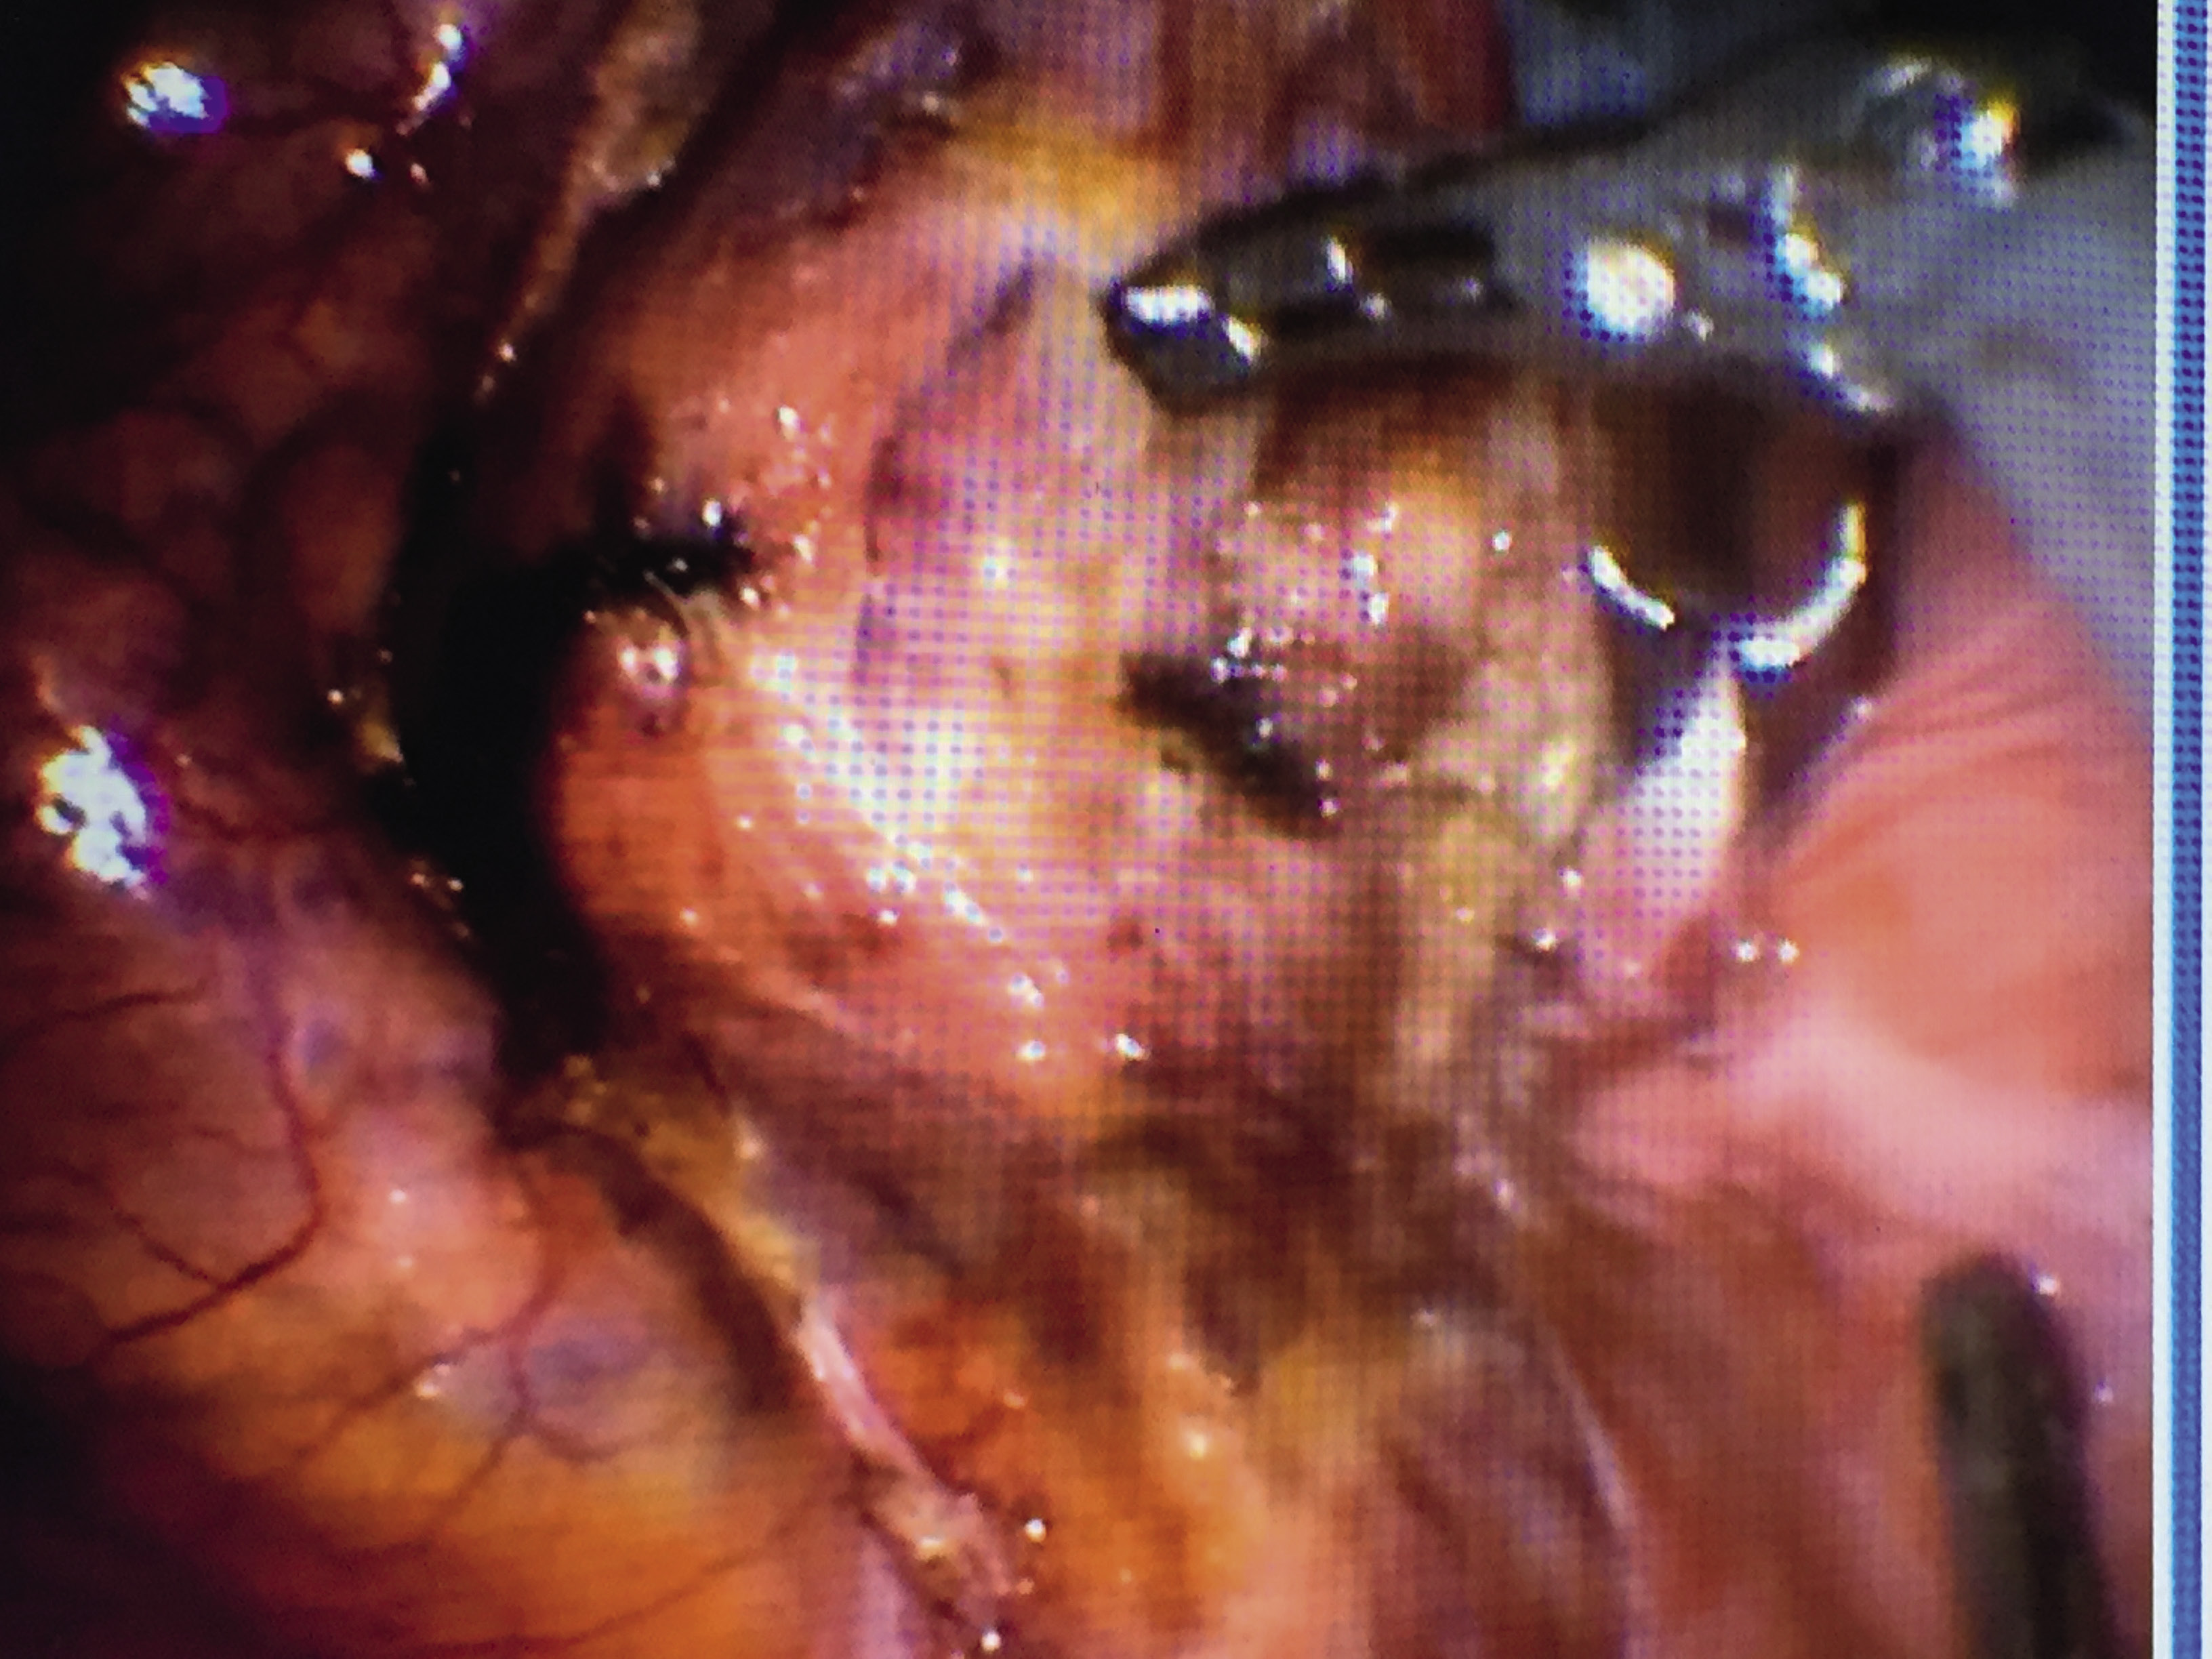

- иссечение соединительной ткани рубца ультразвуковым скальпелем «Harmonik» (рис. 5, 6);

Рис. 5. Иссечение соединительнотканного рубца на матке